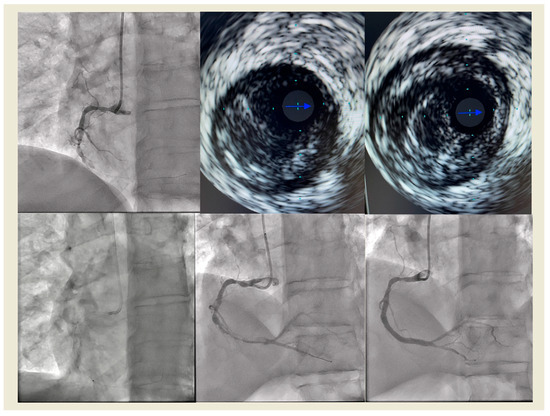

Figure 1

16 pages, 2714 KB

Review

Excimer Laser Coronary Atherectomy: Current Evidence, Clinical Applications, and Future Directions

by Mohsen Mohandes, Alberto Pernigotti, Mauricio Torres, Cristina Moreno Ambroj, Francisco Fernández, Roberto Bejarano-Arosemena, Pablo Moreno, Anna Vidal-Romero, Jordi Guarinos and Jose Luis Ferreiro

J. Clin. Med. 2026, 15(2), 766; https://doi.org/10.3390/jcm15020766 - 17 Jan 2026

Viewed by 181

Abstract

Excimer Laser Coronary Atherectomy (ELCA) has re-emerged as a valuable adjunctive modality in percutaneous coronary intervention (PCI), particularly in the context of increasingly complex coronary anatomy and rising procedural expectations. By delivering pulsed ultraviolet energy at 308 nm through flexible fiber-optic catheters, ELCA [...] Read more.

Excimer Laser Coronary Atherectomy (ELCA) has re-emerged as a valuable adjunctive modality in percutaneous coronary intervention (PCI), particularly in the context of increasingly complex coronary anatomy and rising procedural expectations. By delivering pulsed ultraviolet energy at 308 nm through flexible fiber-optic catheters, ELCA enables precise photochemical, photothermal, and photomechanical ablation of atherosclerotic, fibrotic, calcified, and thrombotic tissue while minimizing thermal injury to surrounding structures. Recent technical refinements, simplified catheter designs, and improved safety profiles have enhanced its feasibility and utility across a range of challenging lesion subsets. This review summarizes the fundamental principles underlying excimer laser–tissue interaction, discusses available equipment and key procedural considerations, and examines the expanding clinical evidence supporting ELCA in contemporary practice. Data from observational studies and multicenter registries suggest that ELCA may enhance device crossability, restore coronary flow, and reduce distal embolization in thrombus-rich lesions, particularly during primary PCI. In device-uncrossable lesions, ELCA facilitates plaque modification and improves procedural success, including in chronic total occlusions. Furthermore, ELCA—especially when performed with simultaneous contrast injection—has demonstrated efficacy in treating stent underexpansion refractory to high-pressure balloon dilation, improving minimal stent area and enabling optimal post-dilatation. As lesion complexity continues to increase, ELCA is gaining recognition as an important tool within the interventional armamentarium. While generally safe in experienced hands, ELCA carries a risk of procedural complications that must be carefully considered. Ongoing investigations are expected to further define its optimal use and reinforce its relevance in modern interventional cardiology. Full article

Show Figures